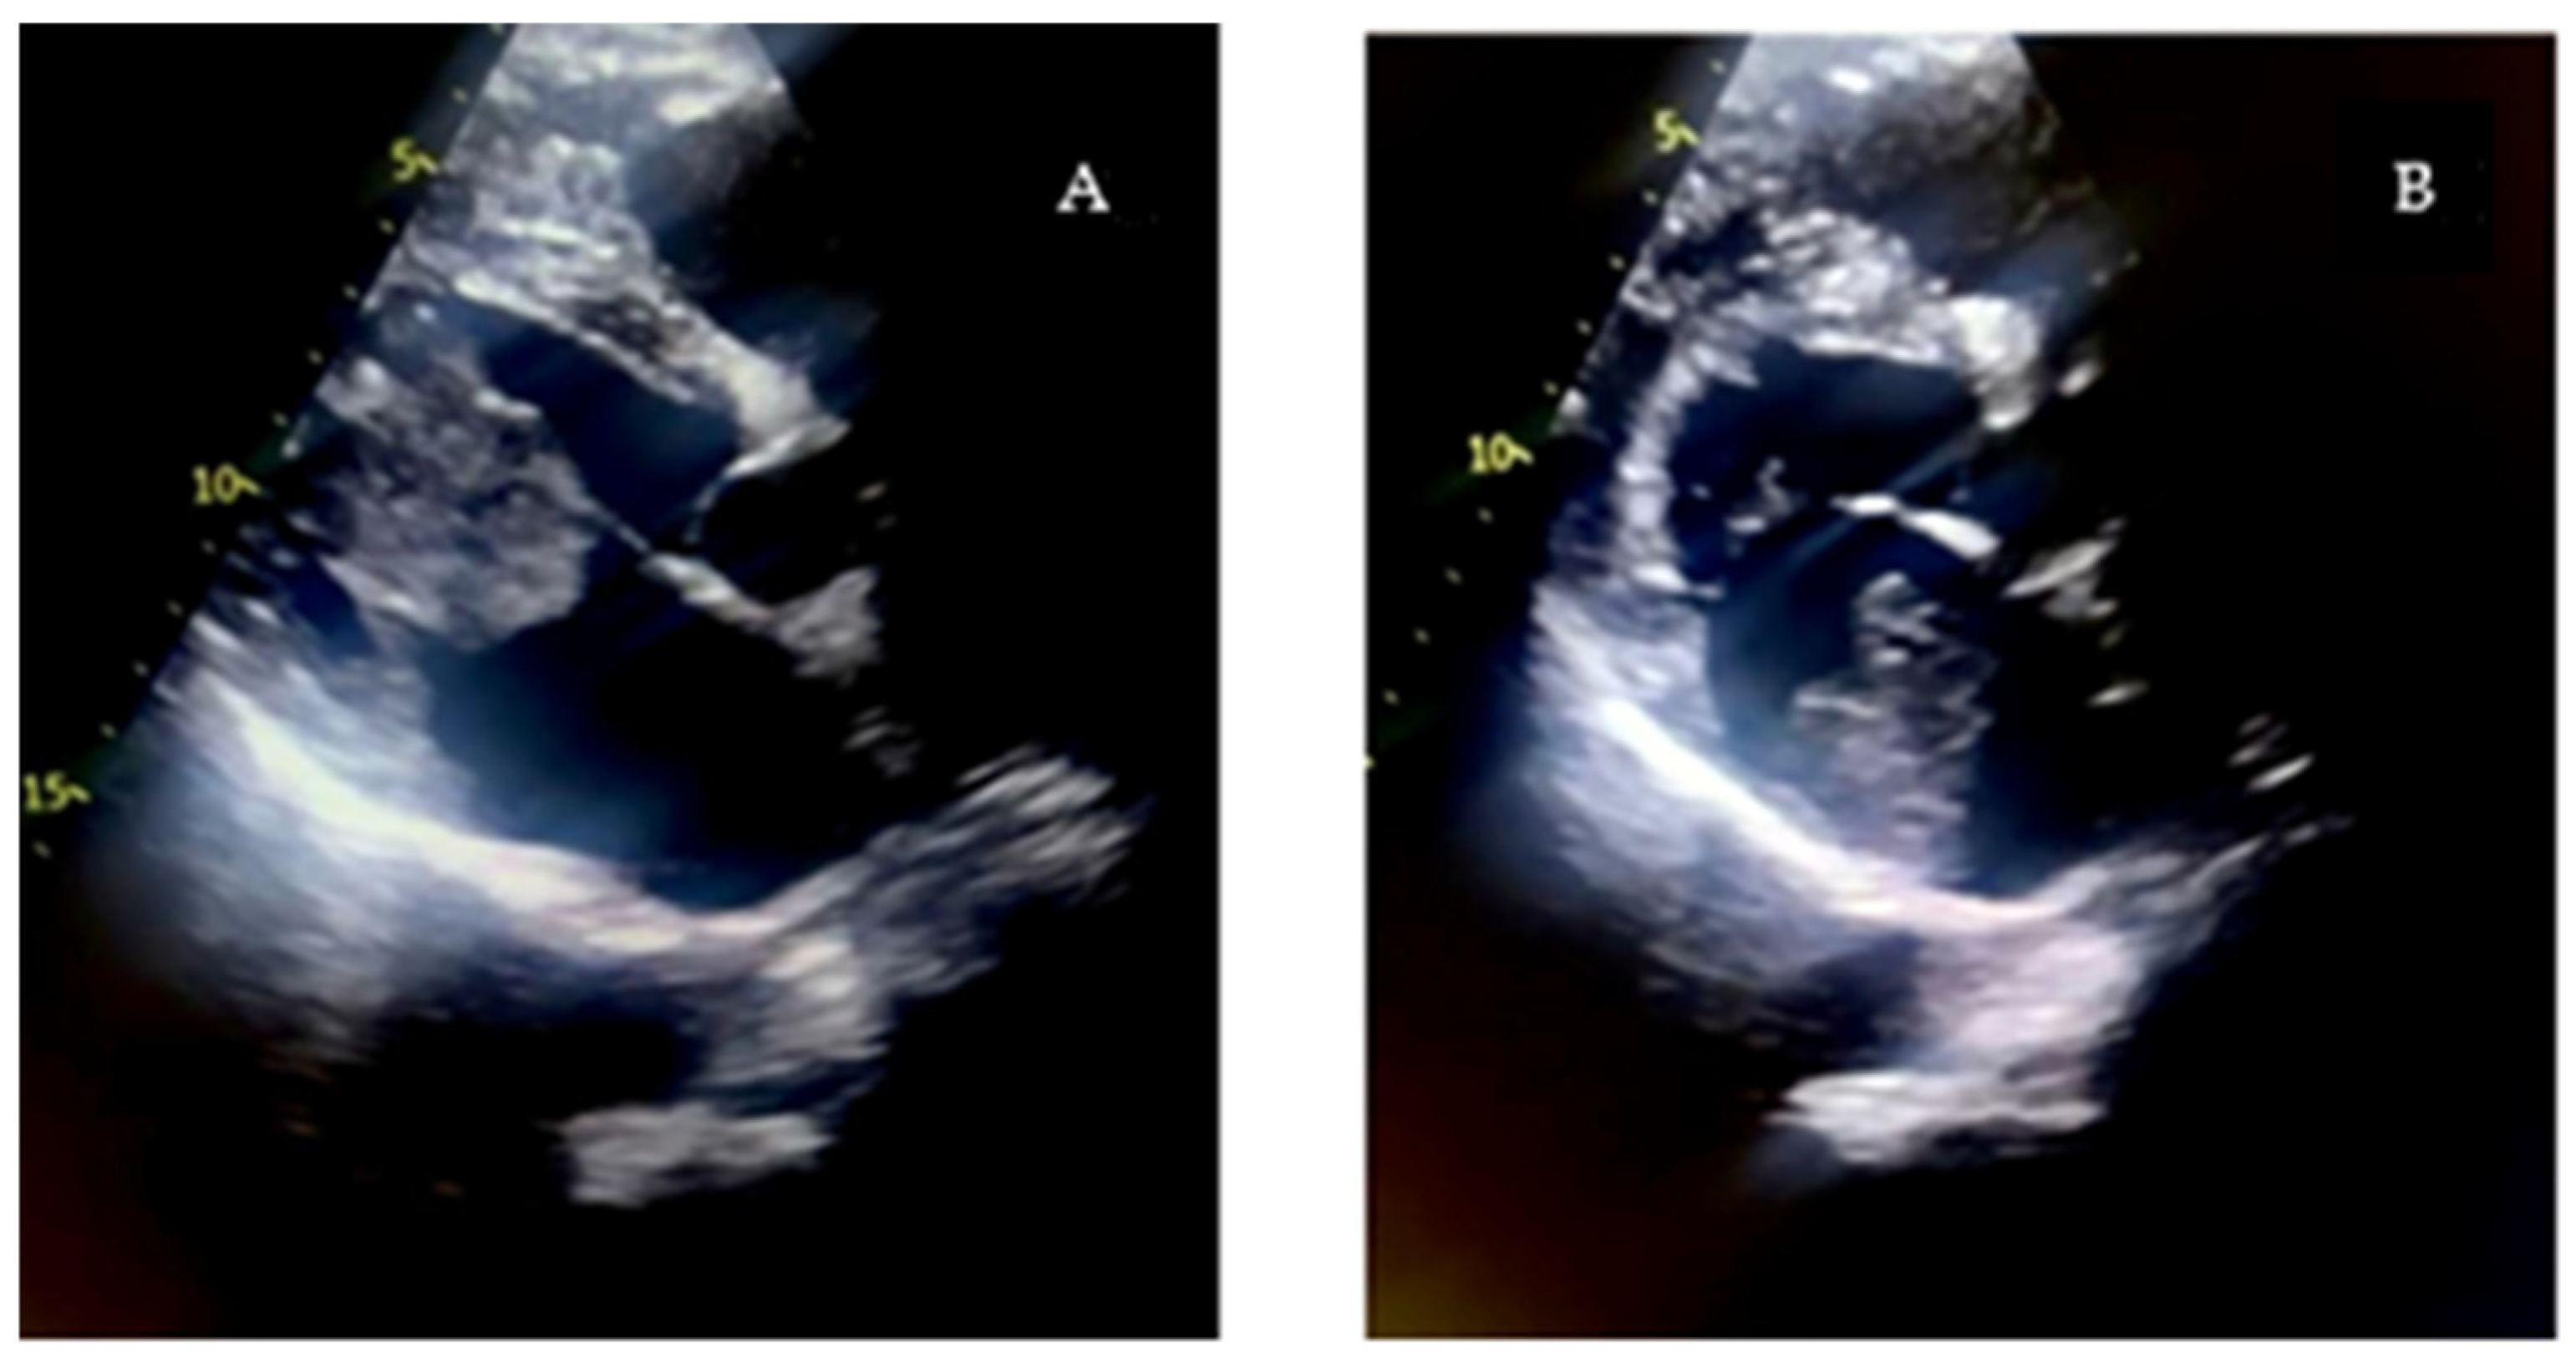

Given the critical obstructive physiology and life-threatening presentation, the patient underwent urgent surgical excision of the mass via median sternotomy under cardiopulmonary bypass (Figure 2). Upon opening the left atrium, a gelatinous mass was identified, attached to the interatrial septum via a narrow pedicle. The tumor measured approximately 3.7 × 4.5 cm and exhibited a lobulated, irregular surface (Figure 3). These findings accounted for the severe dynamic obstruction of the mitral orifice observed preoperatively and underscore the capacity of left atrial myxomas to precipitate acute, life-threatening obstructive disease. Intraoperatively, the mass was friable and gelatinous, with focal areas of increased density suggestive of fibrous components, consistent with a mixed morphological pattern. Its marked mobility and fragile texture raised concern for embolic potential, characteristic of the macroscopic features of cardiac myxomas. The tumor was completely excised at its point of attachment, without requiring interatrial septal resection or reconstruction.

Figure 3. Gross specimen of the excised left atrial myxoma, measuring approximately 3.7 × 4.5 cm, with a lobulated and irregular surface.